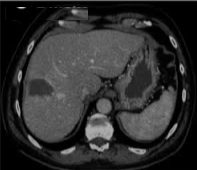

69 岁的男性患者,患有丙型肝炎相关肝硬化,其肝脏增强扫描(S8)中可见一个 22 mm 肝细胞癌结节。